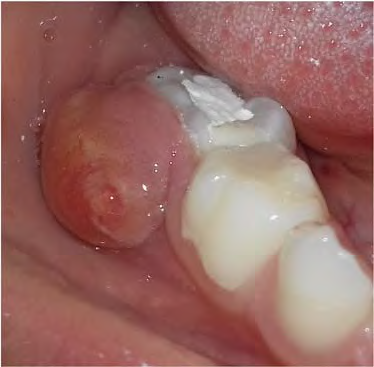

Figura D

Uma criança de 4 anos de idade, afebril e em bom estado geral compareceu para tratamento de urgência em função do surgimento de um nódulo de consistência amolecida e coloração amarelada, medindo 1 cm de diâmetro, localizado na região vestibular do dente 85. palpação do nódulo, houve a saída de secreção purulenta. A mãe informou que, há três meses, a criança havia passado por um atendimento de urgência, e na ocasião, havia sido colocada apenas uma “massinha no dente”.

Com relação a esse caso clínico e aos conhecimentos correlatos, julgue os itens a seguir.

A presença de inúmeros canais secundários na superfície radicular e na área de furca aumenta a possibilidade de repercussões periapicais, a partir da evolução do processo carioso, em dentes decíduos posteriores.

O exame radiográfico, a anamnese e o teste de vitalidade pulpar são essenciais para o diagnóstico e o planejamento do tratamento.

Trata-se de abscesso dento-alveolar agudo, cujo tratamento deve ser realizado por meio da antibioticoterapia, com amoxicilina durante sete dias ou azitromicina durante três dias e, posteriormente, a endodontia do 85.